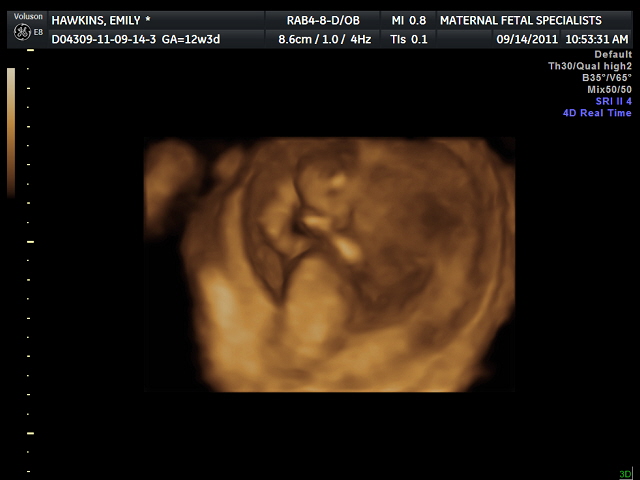

This picture is sort of creepy to me but I must share my 3-D picture. It looks like the baby's sucking it's thumb which I find so cute! I sucked my fingers until I got chicken pox and my mother told me I would get chicken pox in my mouth if I didn't stop. I was 15, no actually I was 5 I think. If this baby is truly a thumb sucker I'm screwed because there's a vaccine for chicken pox now! So many high class problems these days.